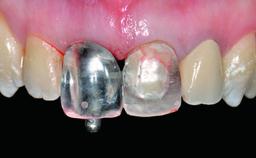

A 32-year-old female Caucasian patient with a compromised maxillary right central incisor was referred to us by a general dentist. Her chief complaints were discomfort and mobility of tooth 11 with unsatisfactory esthetics due to discoloration. The patient reported a previous trauma, some years earlier, as the origin of pathology on the afflicted tooth. Anamnesis was negative for any other dental or periodontal pathology in the remaining dentition. The patient did not take any medication and reported to be a light smoker (5–10 cigs/day). She had high esthetic expectations of her treatment. The extraoral examination revealed a high smile line with full exposure of her maxillary teeth and surrounding soft tissue in the area between the second premolars.